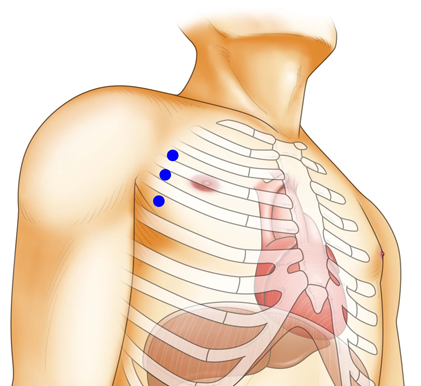

1cmほどのキーホール(鍵穴)を3カ所開け、ロボットアーム(鉗子)や内視鏡カメラを挿入して手術を行います。3D内視鏡カメラにより、術野を鮮明な3D映像で患部を拡大視野で捉えることができ、ロボットの鉗子をミリ単位の操作してオペを遂行します。

ダビンチのキーホール

心臓手術を実施

手術支援ロボット“ダビンチ”を使用した手術を行います。小さな傷口のみの手術なので、早期の社会復帰が可能です。

“ダビンチ”キーホール手術は、手術支援ロボット“ダビンチ(da Vinci Surgical System)”を用いたロボット手術です。開胸することなく、骨を切らず、数カ所のキーホールからすべての操作が遂行できるので、術中の出血が少なく、術後の痛みも軽く、また大きな傷が残らないため美容的にも優れています。従来のように人工心肺などを使用して遂行していた手術が“ダビンチ(da Vinci Surgical System)”の出現により劇的に変化し、術後経過や術中の体への負担が軽減できるようになりました。“ダビンチ(da Vinci Surgical System)”のような内視鏡手術の進歩は心臓だけでなく、すべての領域で目覚ましい発展を遂げています。現在では珍しいものでは無く標準の手術方法として認められる傾向にあり、新たなアプローチとして広い分野で採用されています。

完全内視鏡下外科手術で「切開しない治療」を実現

手術支援ロボット“ダビンチ”を使用したロボット手術は、骨を切らずに小さな傷口のみでオペを行い、出血量・痛みの減少を実現します。早期の社会復帰が可能な手術です。

手術支援ロボットのダビンチによる手術や小切開手術が可能な場合がございます。ダビンチの手術は小さな3つの穴から手術を行うため従来の方法より痛みや傷の感染、出血量が軽減。